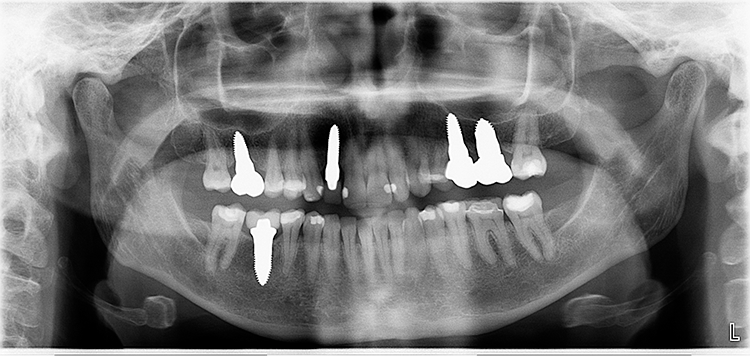

Abb. 2: Repräsentativer Fall von ABH Grad B Septus Typ II. a) Ansichten vor der Installation. Röntgenaufnahme der periapikalen Läsion an einem wurzelkanalbehandelten Molaren und klinische Ansicht der Typ-II-Socket nach der Extraktion. b) Die Ansichten nach der Installation zeigen das Implantat innerhalb des interradikulären Septums und das über dem Implantat platzierte A-PRF. c) Nachuntersuchungen nach 10 Tagen bzw. 2,1 Monaten. Die Röntgenaufnahme zeigt die Knochenbildung zwischen der Sinusmembran und dem apikalen Teil des Implantats. d) Jüngste Nachuntersuchung nach Einsetzen der Prothese.